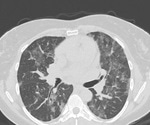

New virtual tool to help the world diagnose COVID-19 in the lungs